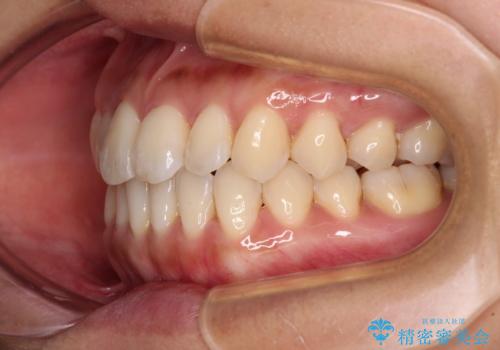

上顎前歯が捻れて前方に飛び出しており、下顎前歯もそれに沿うようにデコボコとなっていました。

IPR(歯と歯の間を削る処置)によりスペースを獲得して上下顎前歯のデコボコを改善し、飛び出している前歯が引っ込むように設定し、インビザラインにて矯正治療を行うこととしました。